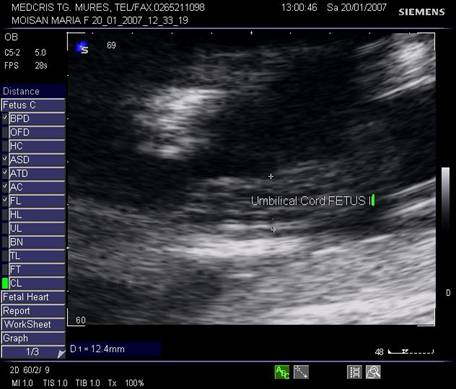

Cordonul ombilical este mult mai mare la fatul acceptor decat la cel donor.

Fig nr 50. Cordonul ombilical al fatului transfuzat , dublu fata de cel al transfuzorului, in diametru ( intre calipere )